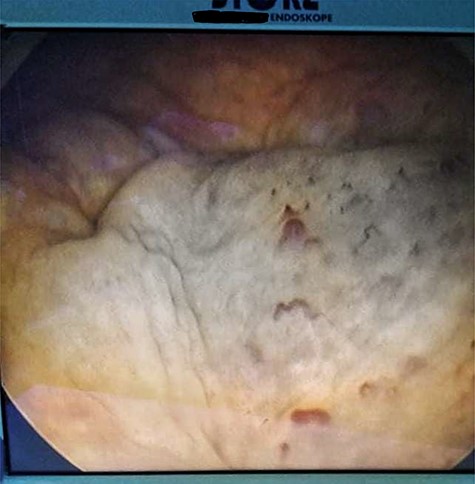

His Hematuria was first explored by abdominal ultrasound, showing an irregular wall thickening in the right lateral face and the floor of the bladder measuring 5 × 3 cm (Fig. 1) with a vascularized appearance (Color Dop and a right hydronephrosis. Computed tomography (CT) scan confirmed ultrasound findings and showed metastatic lymph nodes in both inguinal areas and in internal iliac and latero-aortic areas measuring up to 3 cm and a 4 cm mass in the left adrenal gland (Fig. 2). Digital rectal examination finds a fixed bladder floor. He underwent cystoscopy, which revealed a huge solid non-papillary black pigmented lesion located in the floor and in the right lateral face of the bladder hiding the right ureteral meatus (Fig. 3). Monopolar loop electrocautery was used to excise the tumor as a palliative treatment to stop hematuria. Tumor shavings were particularly blackish (Fig. 4). Pathological examination confirmed the diagnosis of malignant melanoma (Figs 5 and 6). The patient was actually treated with chemotherapy for a metastatic malignant melanoma. Although an evaluation CT scan showed significant progression under chemotherapy of the majority of lymph nodes, our patient is no longer complaining of hematuria or low urinary tract signs.

Cystoscopy showing a solid non-papillary black pigmented lesion of the bladder.